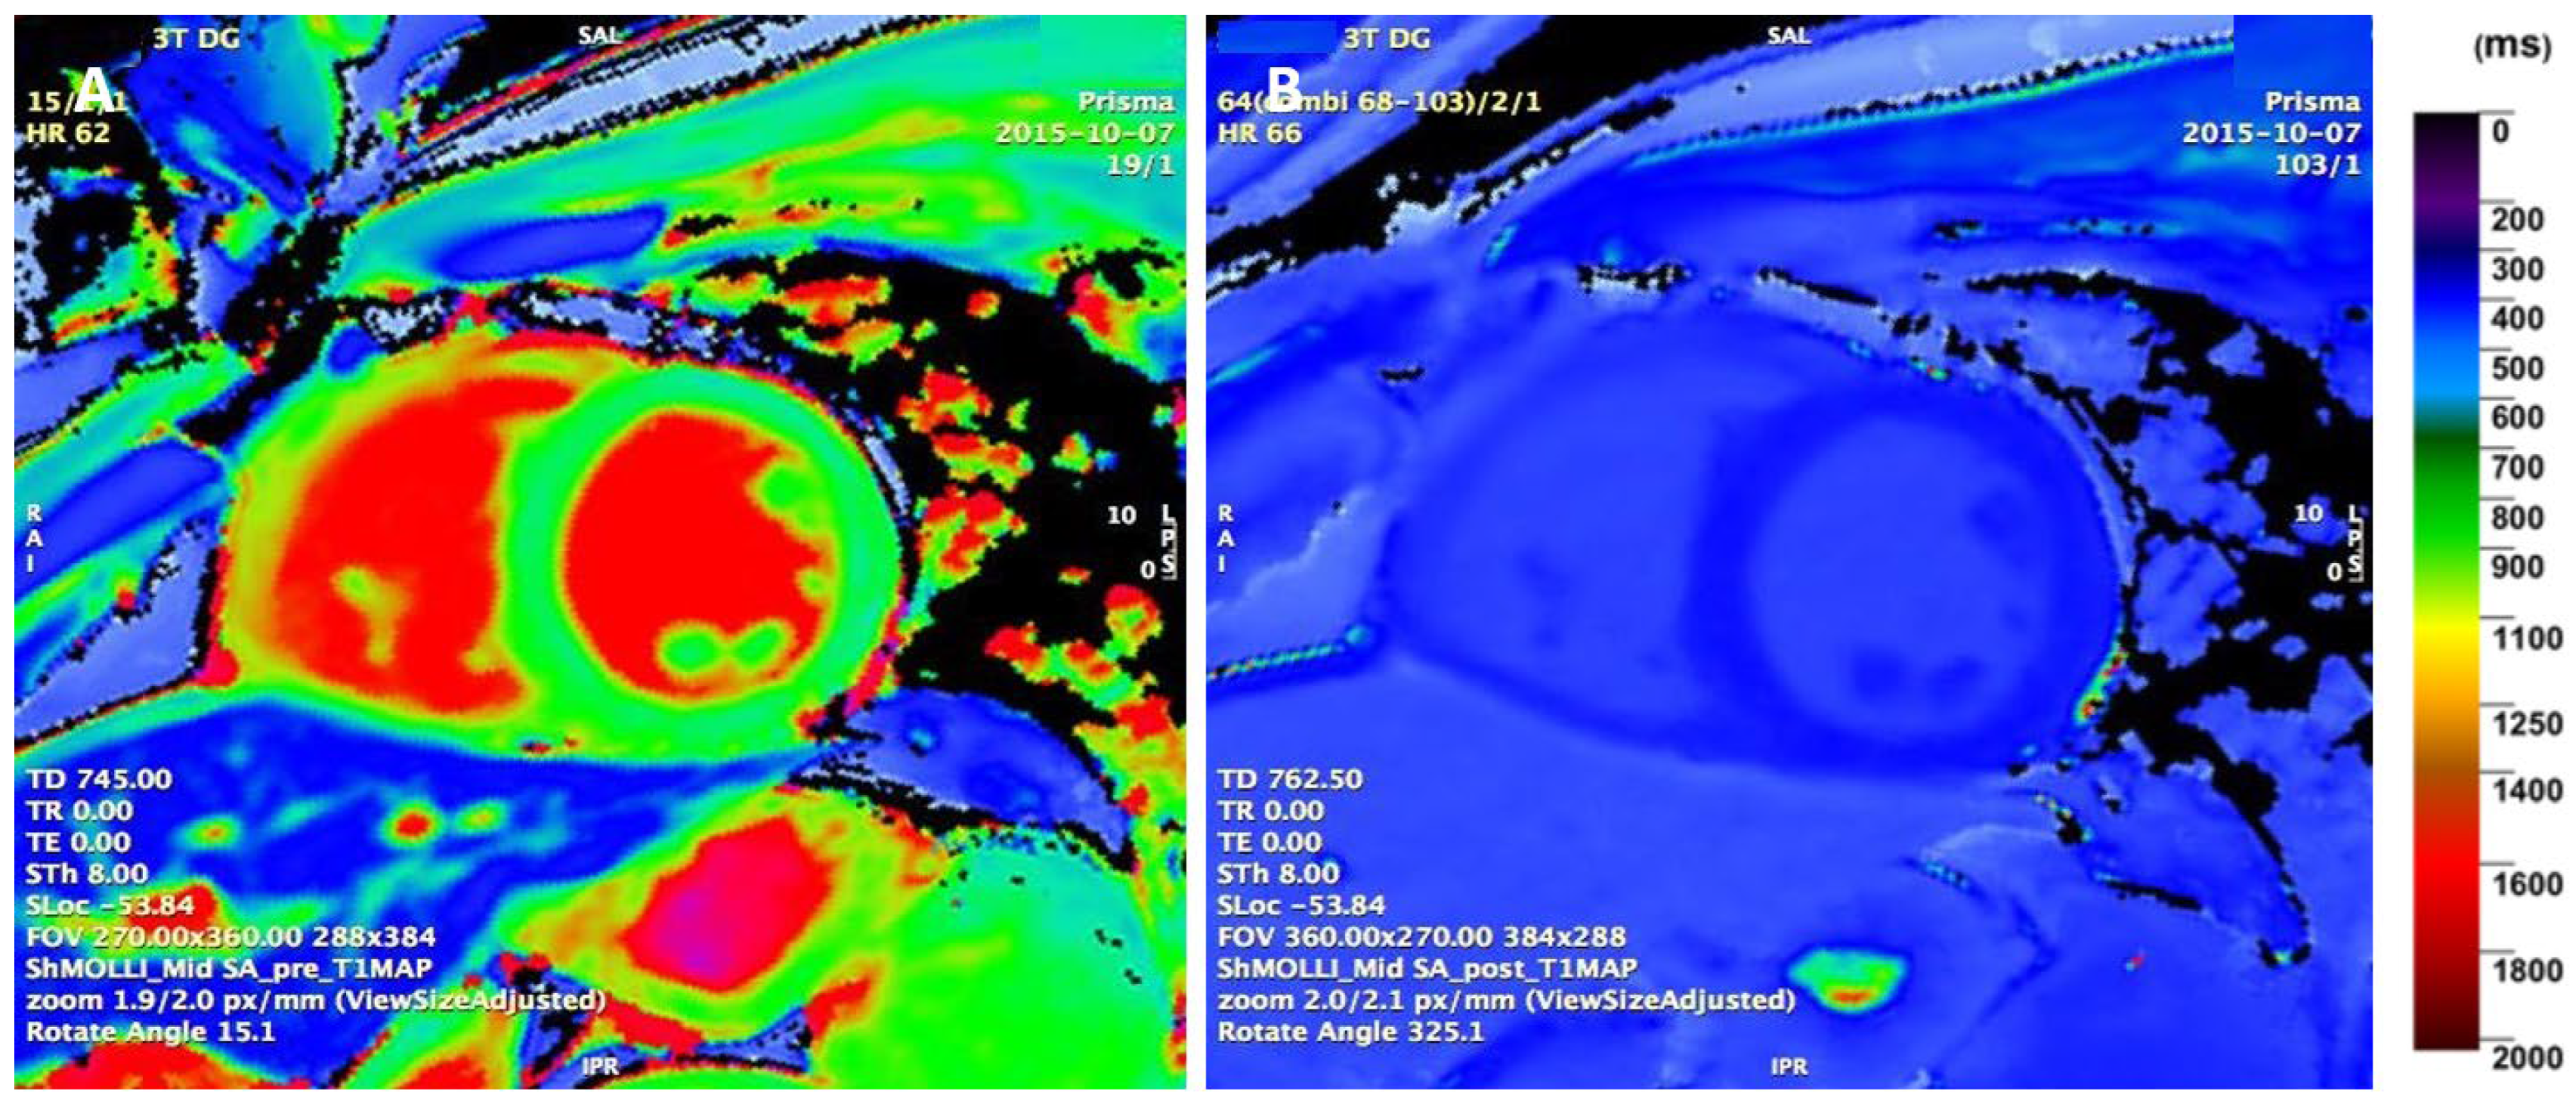

4.3. Parametric T1 Mapping

- Małek, Ł.A.; Barczuk-Falęcka, M.; Werys, K.; Czajkowska, A.; Mróz, A.; Witek, K.; Burrage, M.; Bakalarski, W.; Nowicki, D.; Roik, D.; et al. Cardiovascular magnetic resonance with parametric mapping in long-term ultra-marathon runners. Eur. J. Radiol. 2019, 117, 89–94. [Google Scholar] [CrossRef]

- Swoboda, P.P.; McDiarmid, A.K.; Erhayiem, B.; Broadbent, D.A.; Dobson, L.E.; Garg, P.; Ferguson, C.; Page, S.P.; Greenwood, J.P.; Plein, S. Assessing Myocardial Extracellular Volume by T1 Mapping to Distinguish Hypertrophic Cardiomyopathy from Athlete’s Heart. J. Am. Coll. Cardiol. 2016, 67, 2189–2190. [Google Scholar] [CrossRef]

- McDiarmid, A.K.; Swoboda, P.P.; Erhayiem, B.; Lancaster, R.E.; Lyall, G.K.; Broadbent, D.A.; Dobson, L.E.; Musa, T.A.; Ripley, D.P.; Garg, P.; et al. Athletic Cardiac Adaptation in Males Is a Consequence of Elevated Myocyte Mass. Circ. Cardiovasc. Imaging 2016, 9, e003579. [Google Scholar] [CrossRef] [PubMed]

- Haaf, P.; Garg, P.; Messroghli, D.R.; Broadbent, D.A.; Greenwood, J.P.; Plein, S. Cardiac T1 Mapping and Extracellular Volume (ECV) in clinical practice: A comprehensive review. J. Cardiovasc. Magn. Reson. 2016, 18, 89. [Google Scholar] [CrossRef] [PubMed]